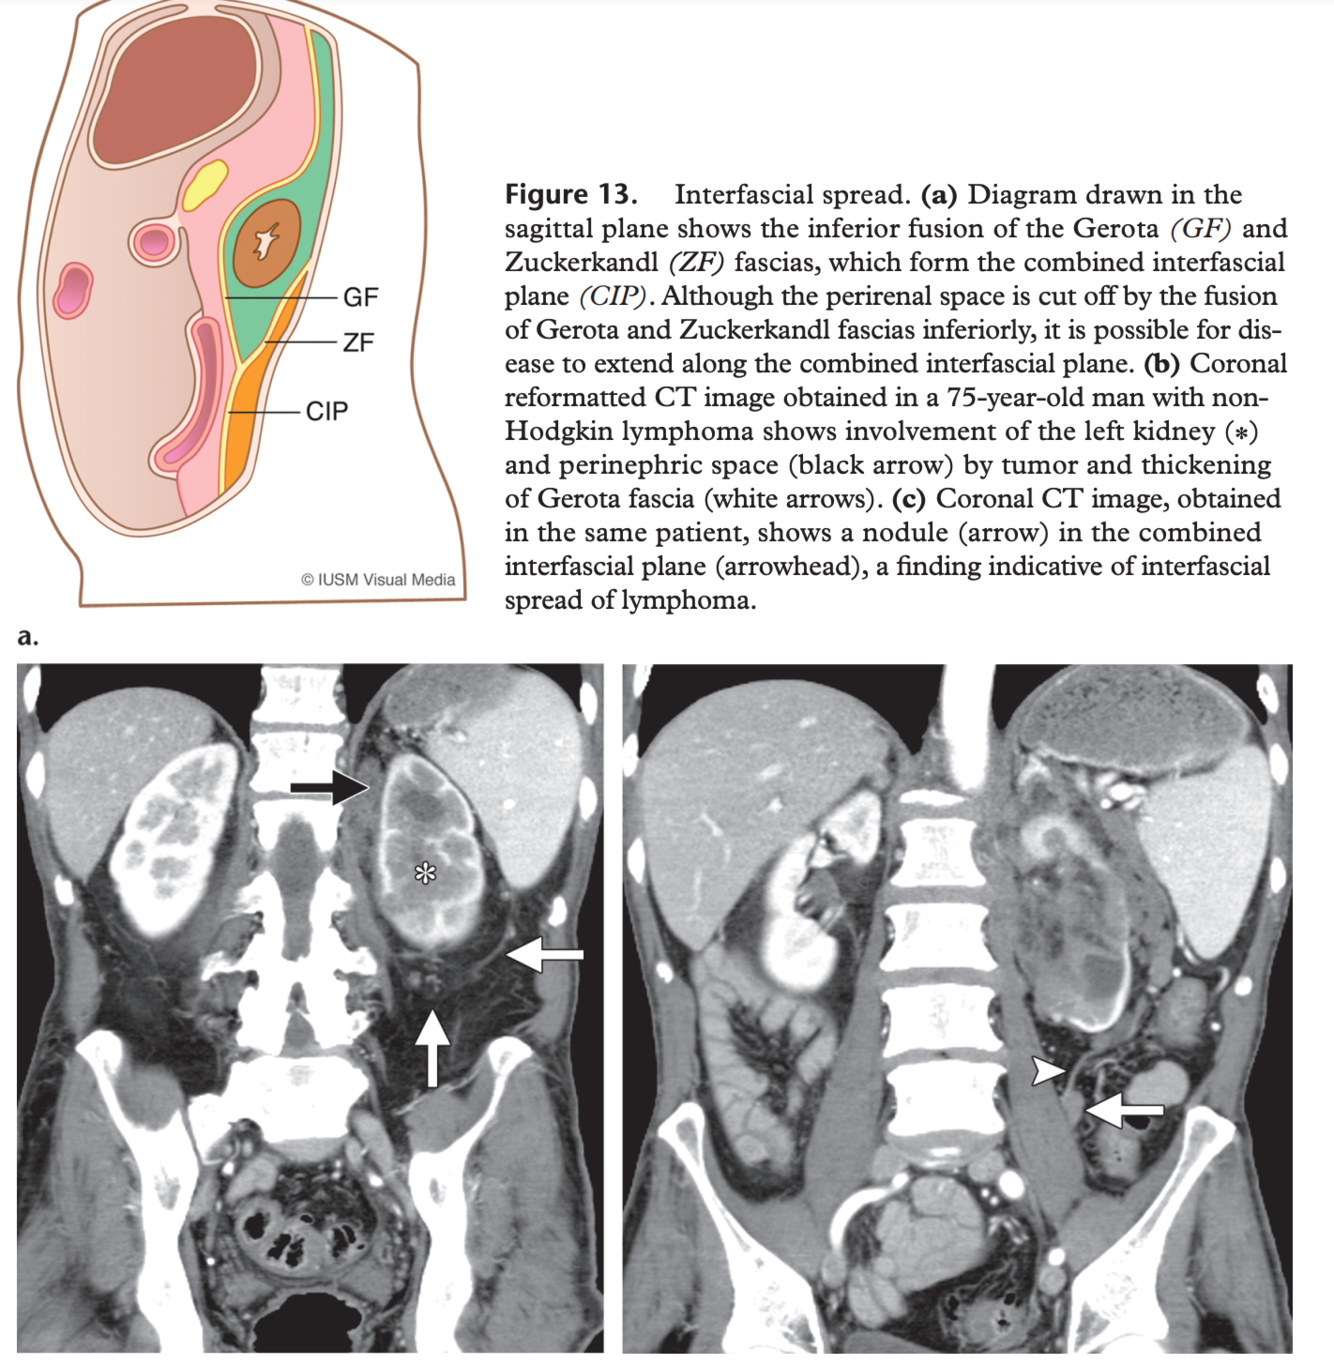

Figure 13. Interfascial spread. (a) Diagram drawn in the sagittal plane shows the inferior fusion of the Gerota (GF) and Zuckerkandl (ZF) fascias, which form the combined interfascial plane (CIP). Although the perirenal space is cut off by the fusion of Gerota and Zuckerkandl fascias inferiorly, it is possible for disease to extend along the combined interfascial plane. (b) Coronal reformatted CT image obtained in a 75-year-old man with nonHodgkin lymphoma shows involvement of the left kidney (*) and perinephric space (black arrow) by tumor and thickening of Gerota fascia (white arrows). (c) Coronal CT image, obtained in the same patient, shows a nodule (arrow) in the combined interfascial plane (arrowhead), a finding indicative of interfascial spread of lymphoma.